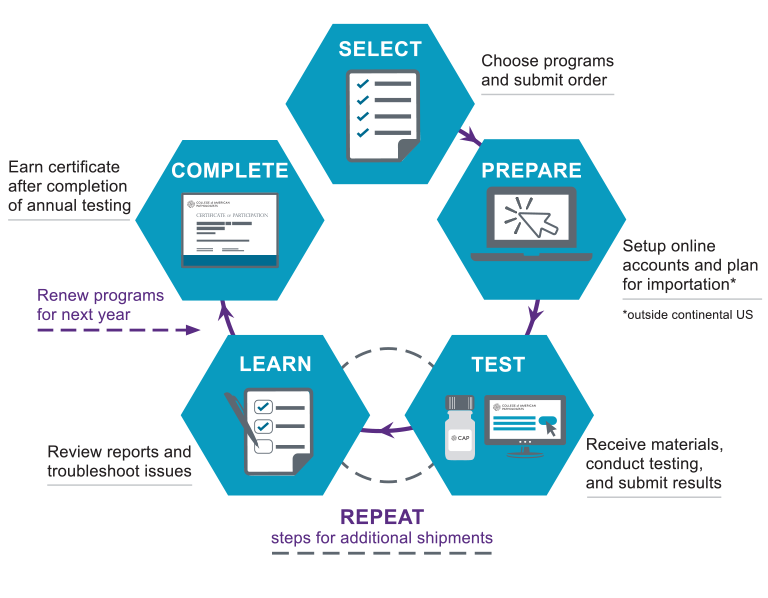

Proficiency Testing Resources College of American Pathologists

Product code: Cap survey discountABS Condition Assessment CAP Program For Aging Vessels discount, Proficiency Testing College of American Pathologists discount, CAP CAS Survey Knowledge Of Sea discount, cap survey PPT discount, Results of Survey on Technology Use CAP Production Process and CAP. Download Table discount, Proficiency Testing College of American Pathologists discount, Survey Says Royal Blue Six Panel Flat Bill Cap Black Maple Trading Co discount, Survey Markers and Caps for Rebar Aluminum Brass Plastic discount, Cap sales survey results discount, cap survey PPT discount, 1 2 or 5 8 Plastic Rebar Cap control point Marker Pack 25 discount, Survey Hat discount, Preparing For An ABS Condition Assessment Program CAP Survey PDF Stress Mechanics Surveying discount, CAP 2013 Surveys and Anatomic Pathology Education Programs discount, ABS Condition Assessment CAP Program For Aging Vessels discount, 2 1 2 Diameter Rebar Caps RBX8250 discount, Condition Assessment Program CAP for Existing Ships discount, 1 2 Plastic rebar cap survey markers discount, PERMAMARK Survey Markers Survey Rebar or 3 4 Pipe Caps discount, 1 2 YELLOW SURVEYORS CAPS SURVEY MARKER SURVEYING BOUNDARY CORNER LINE eBay discount, Plastic Marker Black Letters for 1 2 Rebar or 3 4 Pipe BFPCAP4 0.57 Stakemill Survey Wood Stakes and Survey Markers discount, Condition Assessment Programme CAP discount, Found brass cap What is it Where is it Strictly Surveying Discussion Forums for Land Surveyors discount, Terminology Brass Cap vs. Brass Disk Strictly Surveying Discussion Forums for Land Surveyors discount, CAP Survey LPX A discount, Condition Assessment Programme CAP discount, Proficiency Testing Resources College of American Pathologists discount, Survey Mark Icon Kids Cap Upper Park discount, Location Codes Used in the CAP Survey 11 12 and Reduced Codes Used in THEM Download Table discount, 1 2 or 5 8 Plastic Rebar Cap control point Marker Pack 25 discount, Cap shop survey results discount, Survey Says Royal Blue Six Panel Flat Bill Cap Black Maple Trading Co discount, JCBIZ 12pcs Plastic Reinforced Protective Cap Yellow Safety Mushroom Survey Rebar Cap for Diameter 10 25mm Reinforcement Amazon discount, Attack on Titan Survey Corps Snapback Cap Black Elbenwald discount, College of American Pathologists CAP proficiency testing survey. Key. Download Scientific Diagram discount.